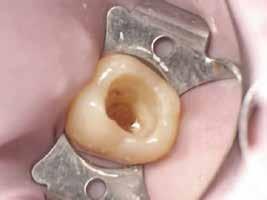

A gyökércsatorna feltágítását és tisztítását hagyományos kemomechanikai protokoll szerint végeztük. Először passzívan levezetett kézi tűk segítségével a gyökércsatornát teljes munkahosszon szondáztuk, ezt követően gépi tágítókkal feltágítottuk, ezalatt nátrium-hipoklorittal öblítettünk, amelyet manuális agitációval aktiváltunk. A gyökércsatorna méretre történő tágítását követően, a következő átöblítőszereket alkalmaztuk: 3 percen keresztül ultrahanggal aktiváltunk 5,25%-os NaOCl oldatot, amelyet közben többször frissítettünk a csatornában, majd váltott átöblítés (17%os EDTA, 5,25%-os NaOCl) a smear layer eltávolítása céljából. Végső átöblítésként 5 percen keresztül ismét 5,25%-os NaOCl oldatot alkalmaztunk, amelyet ultrahanggal aktiváltunk és folyamatosan cseréltünk. A kemomechanikai megmunkálás és az átöblítőszerek alkalmazása során az elszívást a reszorbciós üreg széléhez helyeztük annak érdekében, hogy a kifolyó kémiai hatású szerek ne tudják a környező csont állományt roncsolni.

A gyökértömés elkészítése során meleg vertikális kompakciós technikát alkalmaztunk, sealerként pedig CeraSeal-t (Meta Biomed; 3. ábra) használtunk. A reszorbciós üreget Biodentine-nel (Septodont; 4. a–b ábra) töltöttük fel. A reszorbcióval érintett területtől koronális irányba elhelyezkedő csatornaszakaszt pedig tisztán meleg guttaperchával kezeltük. Ezt követően a lebenyszéleket visszafektettük, és varratok behelyezésével eredeti pozíciójuknak megfelelően rögzítettük. A koronai részt kompozit tömőanyag segítségével állítottuk helyre. Kontrollvizsgálatra 5, illetve 30 hónappal később került sor (5. ábra). A csontos telődés jelei már 5 hónap után észlelhetők voltak (6. a–c ábra). A 30 hónappal később végzett kontroll során sem találtunk csontban lévő lézióra, törésre vagy egyéb pathológiás elváltozásra utaló jeleket (7. a–b ábra)